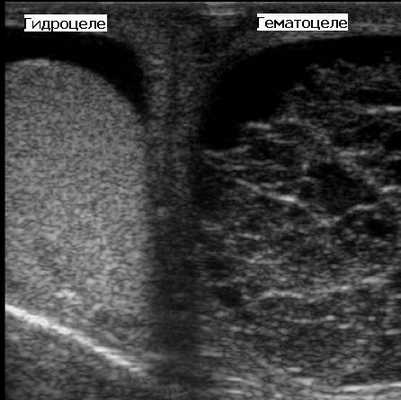

Гидроцеле заполнено серозной жидкостью, именно поэтому при УЗИ оно имеет анэхогенную структуру. Если в полость гидроцеле попадает кровь, такое патологическое состояние носит название гематоцеле. Гематоцеле может возникать в результате травмы мошонки, перекрута, опухолевой инвазии. Пиоцеле - это скопление гноя в полости гидроцеле из-за присоединения инфекции. При УЗИ пиоцеле и гематоцеле - это эхогенные образования, в полости которых со временем могут появляться перегородки, уровни жидкости.

На рисунке слева показано гидроцеле, заполненное серозной жидкостью. А справа визуализируется гематоцеле с большим количеством перегородок.